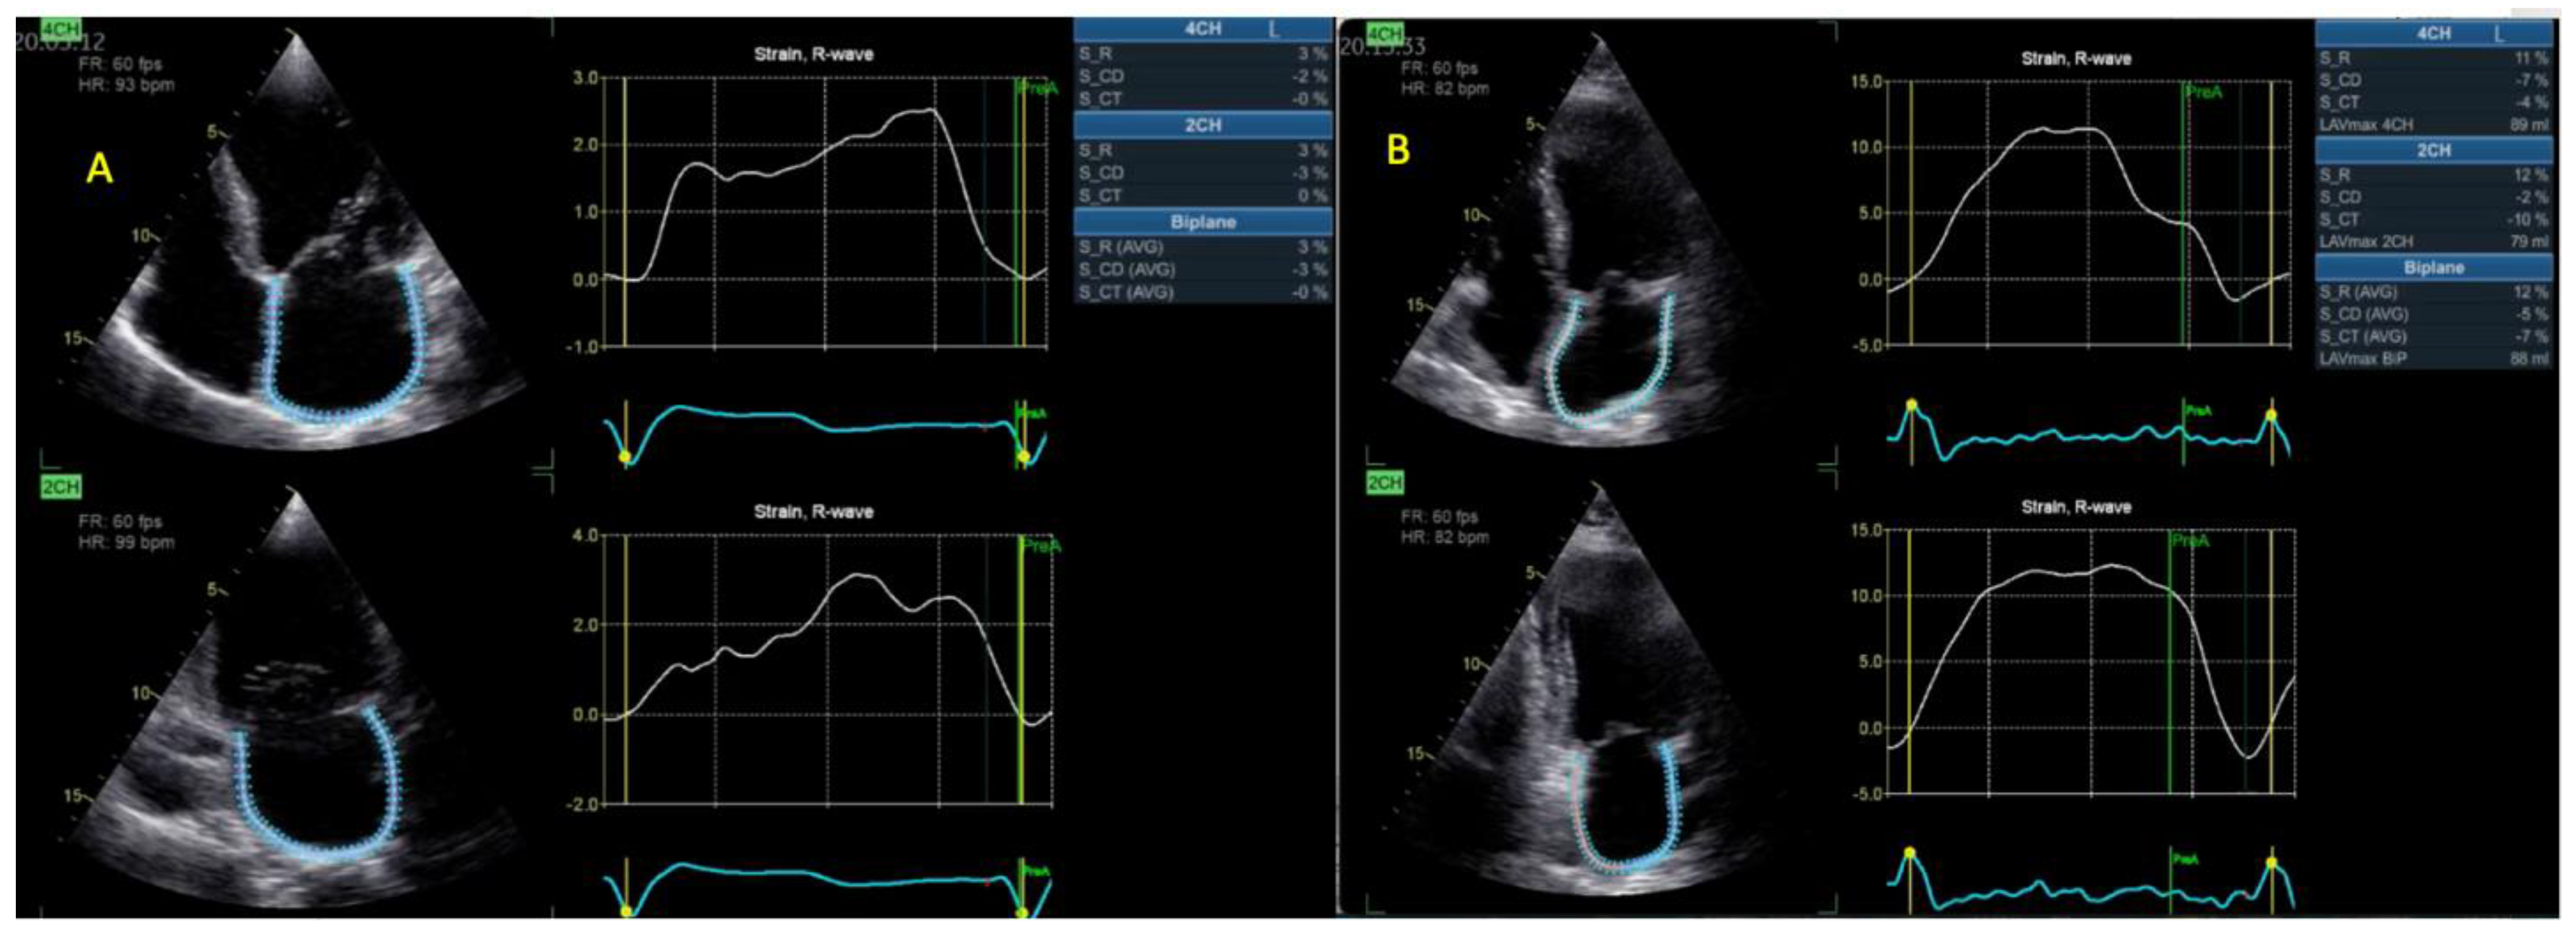

| BP LASr (%) | 12.3 ± 7 | 6.9 ± 3 | <0.001 |

| RVFWLS (%) | 17.2 ± 7 | 13.2 ± 5 | 0.004 |